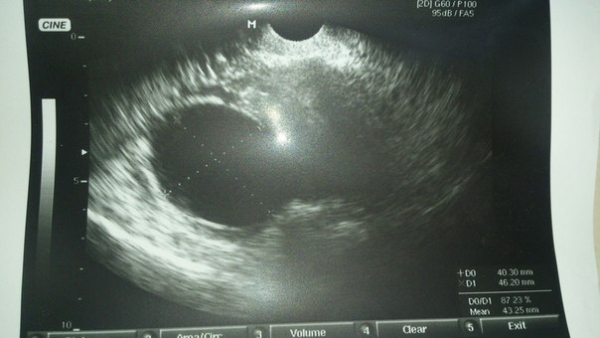

Поймал в проекции правого яичника. Фоликулярная киста ?

Уважаемый Мурад, "голые" УЗ-снимки трудно консультировать, зачастую невозможно дать правильную оценку и заключение. Поэтому при публикации снимков давайте подробное описание увиденного, укажите день цикла и т.п.

Возможно это фолликулярная киста, но виден ли правый яичник? есть ли нарушение цикла? как в режиме ЦДК? и это ещё не все вопросы ..

УЗ-контроль на 5-7 день очередного менструального цикла.

Не похоже на беременность, хотя скорость слишком большая для определения кровотока... Что с тестом на беременность? Желательно контроль через 7-10 дней.